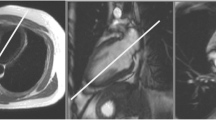

Coronary CTA is performed by the injection of contrast into a peripheral vein, and images are obtained when the contrast reaches the coronary arteries (Fig. 3). The images are acquired relative to the patient’s electrocardiogram (ECG) produced by surface electrodes. The R–R interval of the ECG cycle is typically divided into phases which involve both the systolic and diastolic stages of the cardiac cycle. For most persons, the maximum relaxation of the heart is the best time to acquire images, which is approximately 75% along the R–R interval in mid-diastole. Methods of image acquisition can be either retrospective or prospective.